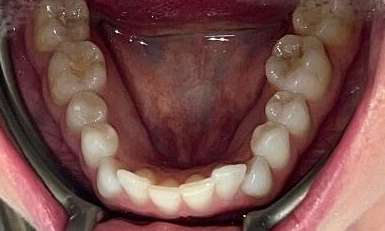

This patient presented with concerns about the damage his teeth had sustained from his bite and previous habits. His lower teeth had caused erosion and wear on the palatal surfaces and incisal edges of his upper front teeth. He was also concerned about the crowding of the lower front teeth. His primary goal was to create a more protected alignment and function of his teeth to support better oral health and longevity.

Due to a sensitive gag reflex, he first trialled nightly whitening trays for two weeks to assess whether he could tolerate aligner wear. This approach helped him proceed with ...